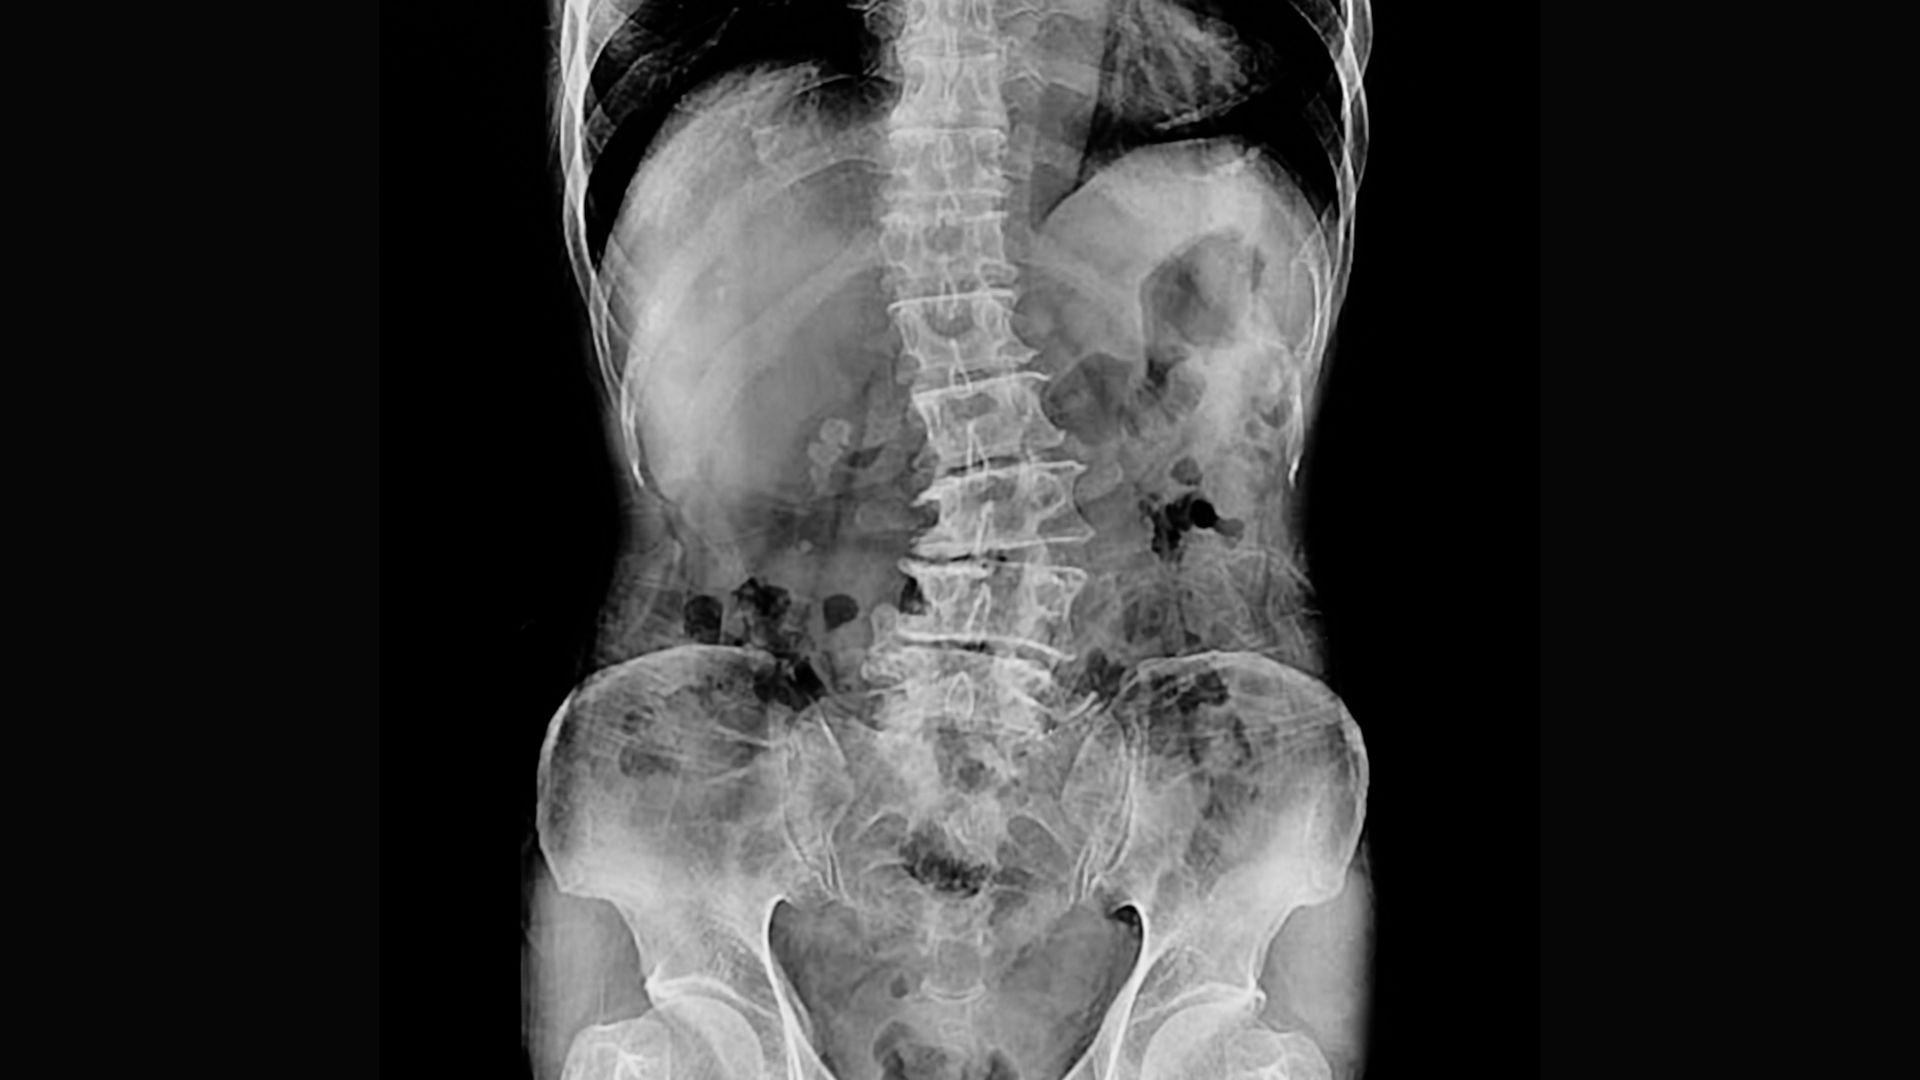

https://www.youtube.com/embed/RlpuIrQvToc Low back pain often results from various forms of sacroiliac dysfunction. Of the ten or so ways the sacrum can become stuck “crooked” between